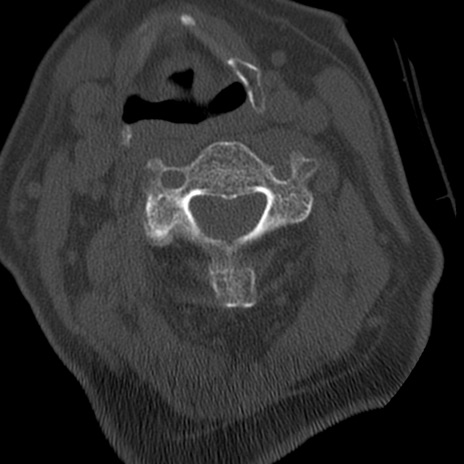

症例50 頚椎CT(横断像)

頚椎CT